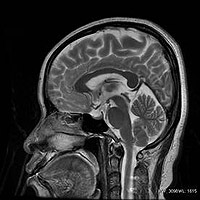

AIR Recon DL画像の一例

脳